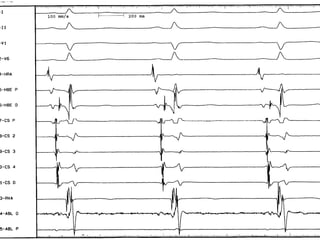

Measurement of basic intervals:Measurement of basic intervals:

PA interval: 20-40ms,PA interval: 20-40ms, from the onset offrom the onset of

the earliest P wave on the surface ECG to thethe earliest P wave on the surface ECG to the

earliest rapid deflection of the atrialearliest rapid deflection of the atrial

electrogram from the His Catheter, measureselectrogram from the His Catheter, measures

atrial conduction.atrial conduction.

AH interval: 50-140ms,AH interval: 50-140ms, representsrepresents

conduction through the AV node to the Hisconduction through the AV node to the His

bundle, measured in the His Catheter,bundle, measured in the His Catheter,

• HV interval: 30-55 ms,HV interval: 30-55 ms, rpresentsrpresents

conduction from proximal His bundleconduction from proximal His bundle

to the ventricular myocardium.to the ventricular myocardium.

• Cycle Length:Cycle Length: (from peak to peak)(from peak to peak)

the R-R interval or the V-V intervalthe R-R interval or the V-V interval